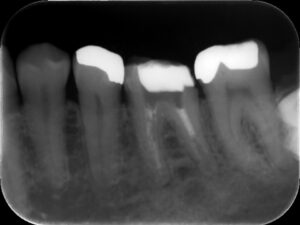

初診時レントゲン。他院にて根管治療を数か月行っているが痛みが続いていると訴えて来院。根管内には依然に詰めた薬がまだ残っているように見える。根尖部の骨破壊はほとんど認めない。